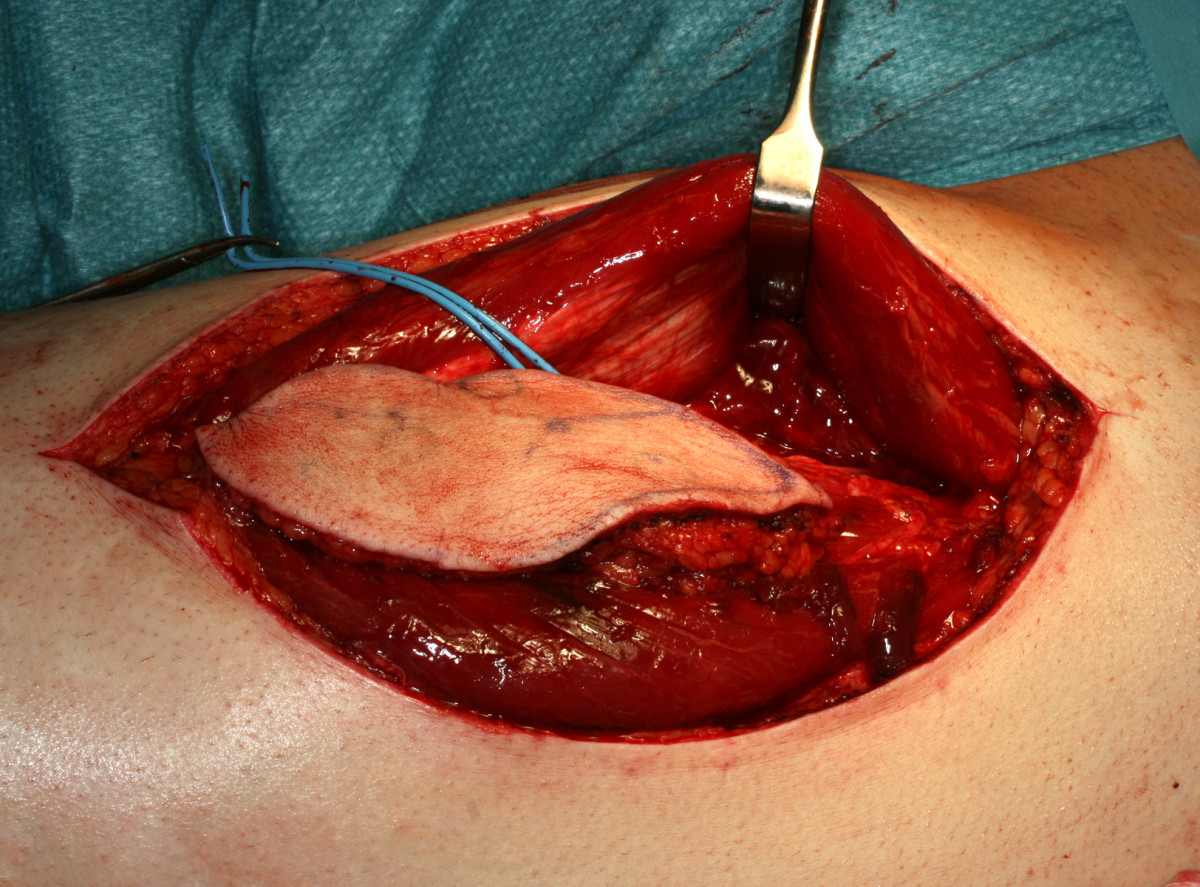

The overall survival rate of our patients with tongue cancer still lies within the range of survival rates decriped by other authors, which are quoted between 40 and 65%(7)(8)(9)(11)(24). We have to keep in mind that our study reviews a period of three decades and that treatment strategies have changed during this period towards a more aggressive course(43)(44). On the base of our results with high locoregional recurrence rates even in early stages of tongue cancer, we generally recommend extended resections on the primary site and categorical bilateral lymphadenectomy of at least level I-III in order to reliably remove occult lymph node metastases which can not be detected even by modern imaging techniques. In case of an open staging procedure with histologically approved lymph node metastases during surgery, a comprehensive neck dissection should complete lymphadenectomy(45). As described before, neck dissection procedures are only associated with a low morbidity(46). Modern reconstructive techniques with microvascular tissue transfer [Figure 12] help to keep functional impairment after partial glossectectomy tolerable and at least allow to refill substancial loss of soft tissue after total glossectomy(47) [Figure 13]. According to our results, radical surgery also provides considerable survival rates for advanced stages of tongue cancer and should be recommended as treatment of first choice. Adjuvant treatment modalities should be applied more frequently in controlled clinical trials and should generally be implemented in cases with unclear margins and lymphatic spread.

Figure 12 Thumb

Figure 12. Harvested anterolateral thigh flap (ALT-flap) based on the perforator vessels of the descending branch of the lateral circumflex femoral artery for reconstruction of the right toung.

Click image to view larger.